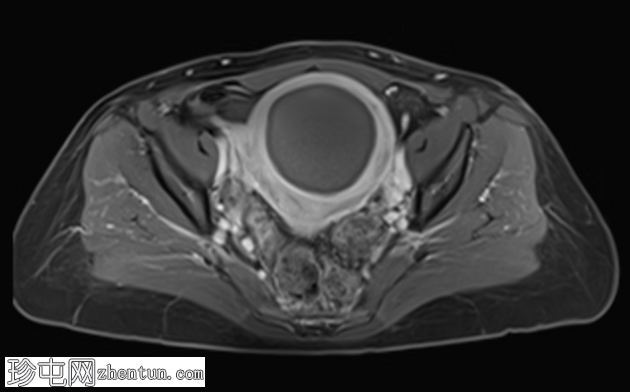

轴位T2加权像

脂肪抑制

子宫前壁可见一边界清晰的壁内病灶,大小约7.8 × 7 × 6.8 cm。脂肪抑制T1加权像呈弥漫性高信号,T2加权像呈高信号伴低信号环,无扩散受限及对比增强。

此外,可见一个2厘米的带蒂浆膜下肌瘤,以及较小的肌壁内和浆膜下肌瘤;所有肌瘤均呈均匀强化。

盆腔内可见少量游离液体,可能为生理性。

未发现明显淋巴结肿大。

红色(出血性)变性是一种出血性梗死,由子宫肌瘤周围静脉回流受阻(静脉血栓形成)或瘤内动脉破裂引起。它最常与妊娠期间肌瘤快速生长或服用口服避孕药有关。

MRI可对子宫肌瘤进行准确诊断和定性,包括识别出血性(红色)变性等罕见并发症,并有助于将其与其他可能需要手术治疗的疾病区分开来。